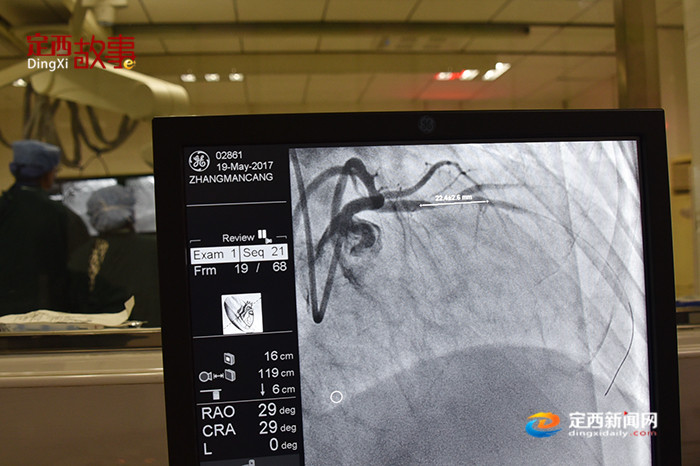

1/10 介入治疗是在不开刀暴露病灶的情况下,在血管、皮肤上作直径几毫米的微小通道,或经人体原有的管道,在影像设备(血管造影机、透视机、CT、MR、B超)的引导下对病灶局部进行治疗的创伤最小的治疗方法。而随着介入诊疗的普及,介入医务人员的辐射安全已成为介入工作发展中一个不可回避的问题。

9/10 介入手术中所用的导丝,可以由医生操作进行灵活弯曲和转向,它将通过右手桡动脉穿越复杂的血管,在一路到达目的地的过程中,医生需要通过X光透视来掌握情况,辐射便在这个过程中产生。

5/10 周杰尚:兰大二院定西医院心脏中心主任医师,在全市率先独立开展了永久性心脏起搏器植入术、床旁临时心脏起搏术、冠状动脉造影术、冠状动脉球囊扩张加支架植入术、心包穿刺置管引流术、急性心肌梗死等的急诊冠脉介入治疗。每次手术,他都要负担40斤左右的铅制隔离设备,一台手术下来就会汗流浃背。若在炎热的夏季, 或者手术量增多,对医生的体力更是相当大的考验。